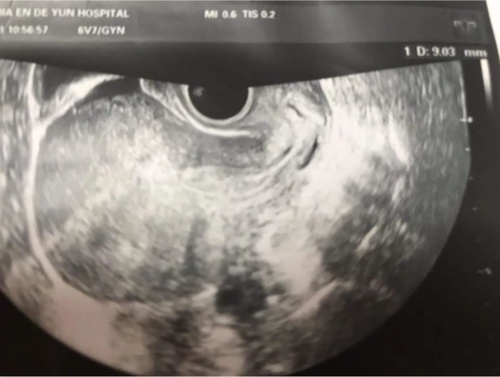

如果女性有宫腔息肉的话,在经过b超检查的时候,b超会提示宫腔内有轻微的回声,这样的情况就可以考虑有宫腔息肉。因为b超对宫腔息肉和宫肌瘤不容易区分,所以建议做宫腔镜检查会更加的准确,并且还可以同时进行治疗。

对于宫腔息肉最直接的检查应该是宫腔镜,宫腔镜既能很好的看见息肉的位置,大小,数量,也能同时进行切除,在进行切除以后,建议是送往病理科进行检验的,以免出现病变的情况,在做完治疗以后,女性要及时的进行休息,并且还要调理自身的饮食。